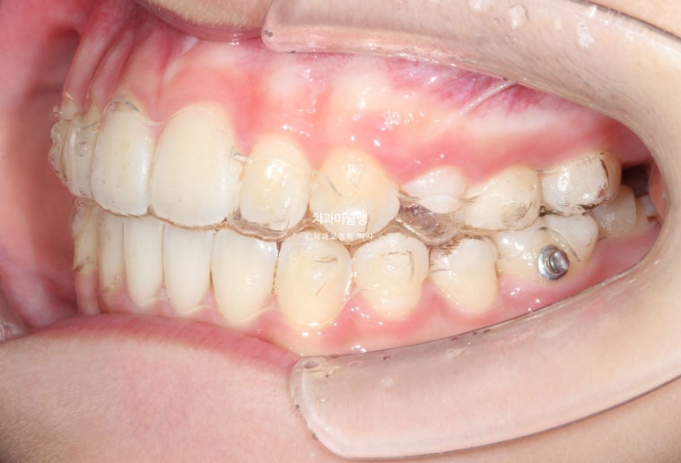

25.11

중심선은 잘 맞고 배열도 좋습니다.

그 사이 마지막 작은어금니까지 모든 영구치가 나와 교합이 완성이 되었습니다.

1급 물샐틈 없는 교합관계를 보입니다.

총 치료기간은 1년 6개월이고 중간에 영구치 나오기를 기다리며 쉬는 시간이 7개월이고 액티브하게 장치를 열심히 끼던 시간이 약 11개월입니다

재제작은 총 1회 했습니다.